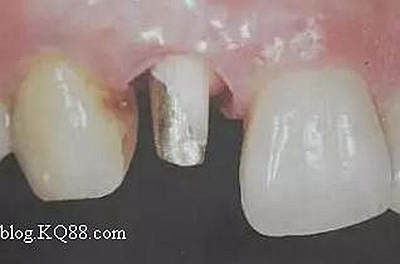

如下圖剩余的組織就過(guò)于薄弱,以后也是一個(gè)安全隱患。

2、去除暫封物。